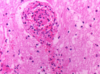

What is this structure and what is it’s function?

Choroid plexus

Function: produces CSF within the ventricles